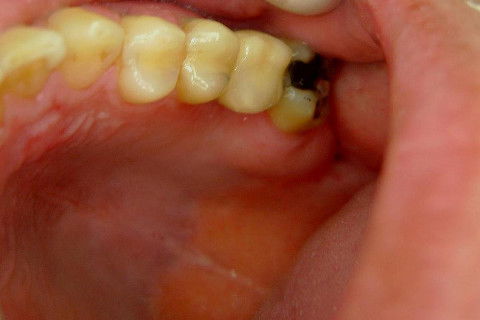

Instalação de um implante em região do 26. Utilizamos um implante cone morse Alvim Neodent 4.3 X 11,5. Foi uma cirurgia muito rápída e minimamente traumática, sem retalho e sutura.